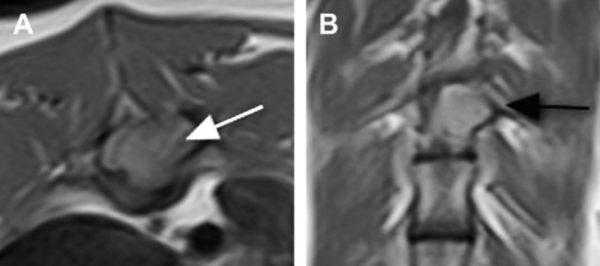

- интрамедуллярные опухоли — формируются из клеток мозгового вещества и растут внутри спинного мозга;

- экстрамедуллярные опухоли могут быть экстрадуральными (располагаются над твёрдой мозговой оболочкой) и интрадуральными, или субдуральными (локализуются под твёрдой мозговой оболочкой).

3. Магнитно-резонансная томография (МРТ) с контрастным усилением. На данный момент это основной метод диагностики новообразований спинного мозга. МРТ позволяет визуализировать весь спинной мозг и позвоночник и определить локализацию опухоли. Накопление контрастного вещества определяет не только распространение, но и гистологическую структуру опухоли [5] [6] .

С клинической и анатомической точки зрения опухоли могут быть классифицированы как опухоли эпидуральные, интрадуральные экстрамедуллярные и интрамедуллярные.